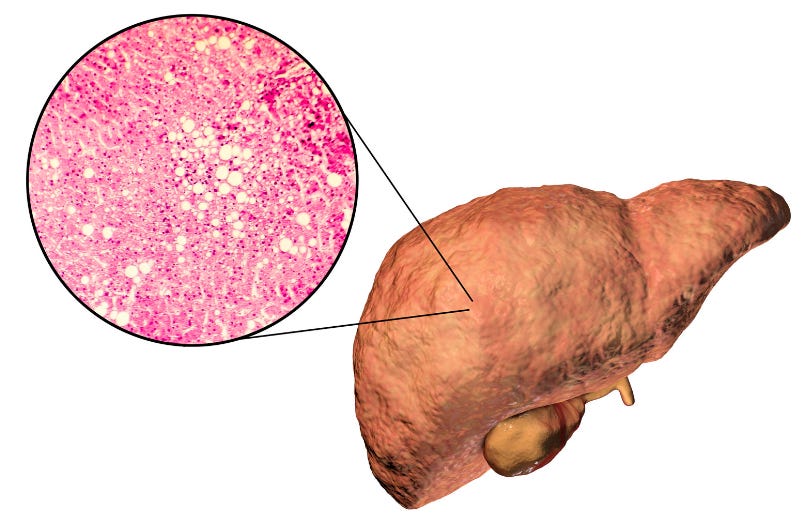

Esteatose hepática no US de abdome: devemos prosseguir investigação?

Hoje sabemos que o US de abdome é quase uma rotina em nosso consultório: indicado para pacientes com sobrepeso ou diabéticos para investigação de esteatose hepática.

O problema é que muitas vezes paramos por aí: sem prosseguir a investigação da esteatose e estabelecer os pilares para o tratamento.

Esse foi o tema do DozeCast da última semana, em parceria com a Mantecorp, onde discutimos tudo sobre a síndrome metabólica, a investigação e o tratamento da esteatose hepática.